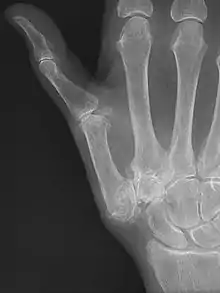

Diagnosis

TMC OA is diagnosed based on symptoms and signs.[8] Radiographs can confirm the diagnosis and the severity of TMC OA. Other diagnoses in this region include scaphotrapezial trapezoid arthritis and first dorsal compartment tendinopathy (De Quervain syndrome) although these are usually easy to distinguish.

TMC OA severity was classified by Eaton and Littler which can be simplified as follows:[21][22]

Stage 1:

- slight widening of the joint space

- < 1/3 subluxation of the joint (in any projection)

Stage 2:

- Osteophytes, < 2 mm in diameter, are present. (usually adjacent to the volar or dorsal facets of the trapezium)

Stage 3:

- Osteophytes, > 2 mm in diameter, are present (usually adjacent to the volar and dorsal facets of the trapezium)

- Slight joint space narrowing

Stage 4:

- Narrow joint space

- Concomitant scaphotrapezial arthritis

A simpler classification is no arthritis, some arthritis, and severe arthritis.[23] This simpler classification system omits the potentially contradictory details of the Eaton/Littler classification and keeps scaphotrapezial arthrosis separate.